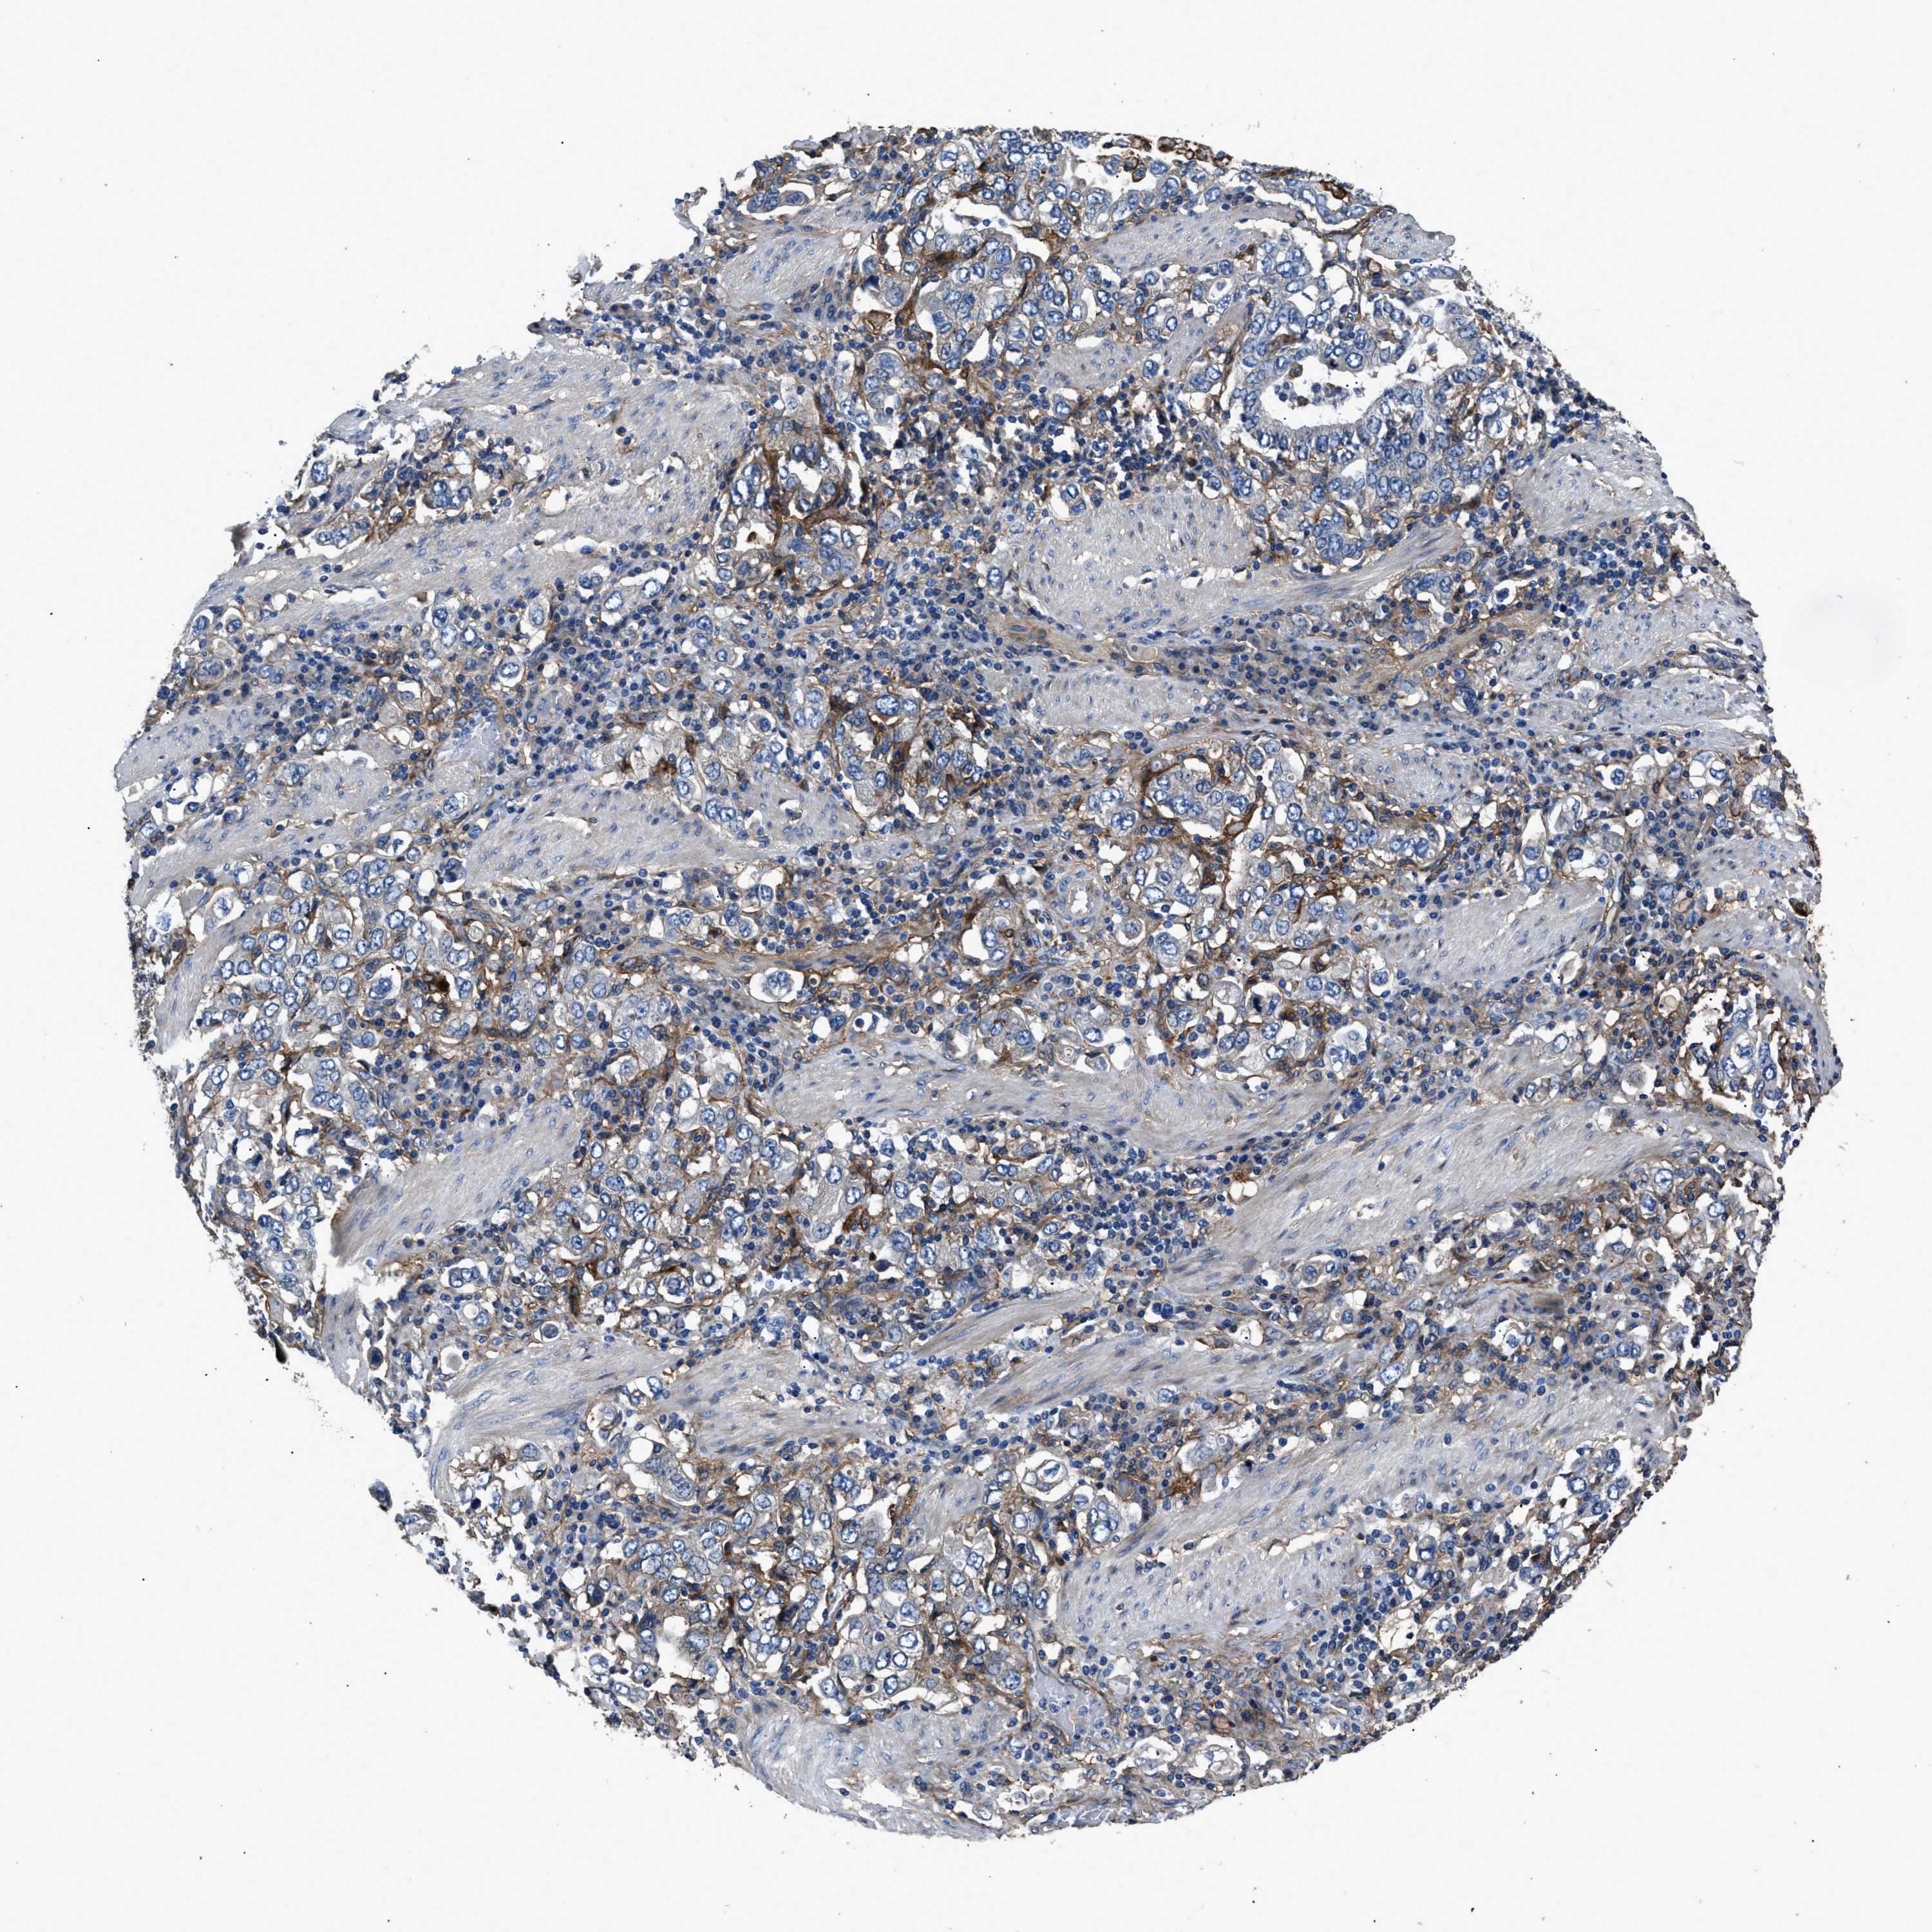

STOMACH CANCER - Protein expressioni

A mouse-over function shows sample information and annotation data. Click on an image to view it in a full screen mode. Samples can be filtered based on level of antibody staining by selecting one or several of the following categories: high, medium, low and not detected. The assay and annotation is described here.

Note that samples used for immunohistochemistry by the Human Protein Atlas do not correspond to samples in the TCGA dataset.

Antibody stainingi

Antibody staining in the annotated cell types in the current human tissue is reported as not detected, low, medium, or high, based on conventional immunohistochemistry profiling in selected tissues. This score is based on the combination of the staining intensity and fraction of stained cells.

Each image is clickable and will lead to virtual microscopy that enables deeper exploration of all samples and also displays staining intensity scores, fraction scores and subcellular localization as well as patient and tissue information for each sample.

Antibody HPA009285

Antibody HPA017139

Antibody CAB017826

Staining

High

Medium

Low

Not detected

Intensity

Strong

Moderate

Weak

Negative

Quantity

>75%

75%-25%

<25%

None

Location

Nuclear

Cytoplasmic/membranous

Cytoplasmic/membranous,nuclear

Adenocarcinoma, NOS

Adenocarcinoma, High grade